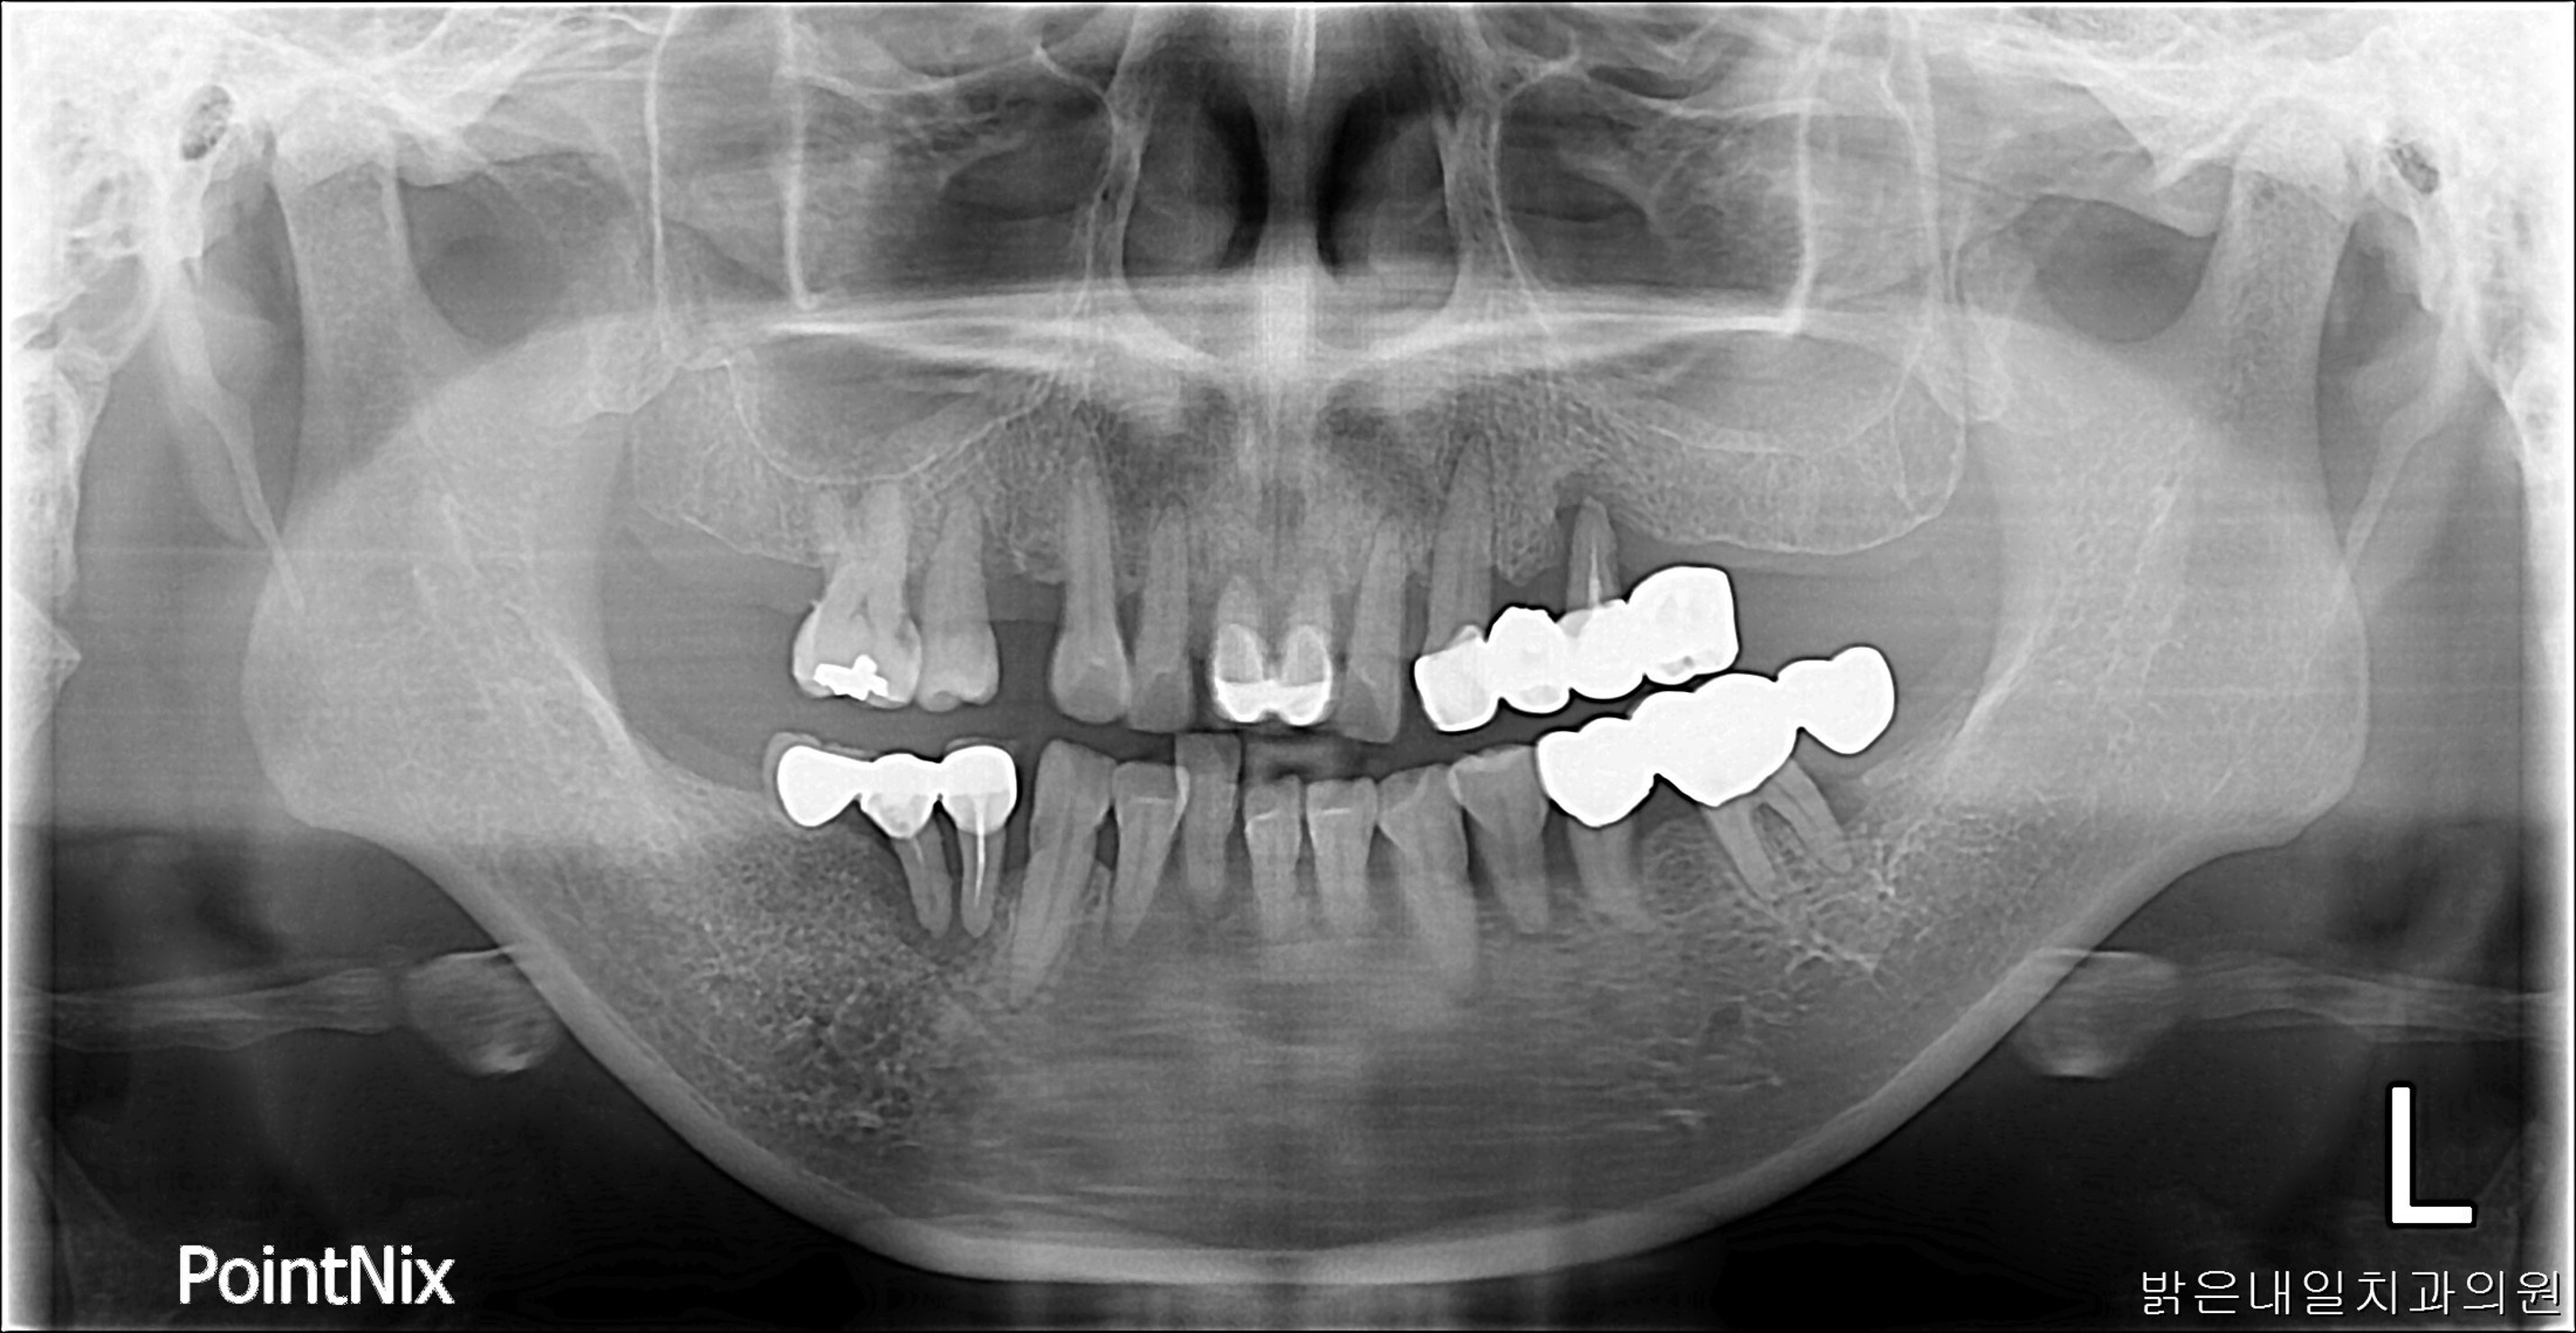

Before

남아있는 치아들이 모두 흔들리거나 썪어서 제거 후 전체 임플란트를 시술한 모습입니다.